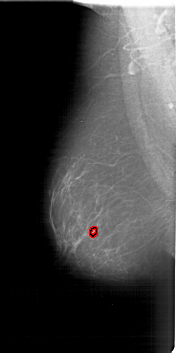

A_1800_1.LEFT_CC

LEFT_CC LINES 6841 PIXELS_PER_LINE 3466 BITS_PER_PIXEL 12 RESOLUTION 43.5 OVERLAY

FILE: A_1800_1.LEFT_CC.OVERLAY

TOTAL_ABNORMALITIES 1

ABNORMALITY 1

LESION_TYPE MASS SHAPE LOBULATED MARGINS ILL_DEFINED

ASSESSMENT 4

SUBTLETY 3

PATHOLOGY BENIGN

TOTAL_OUTLINES 1

BOUNDARY